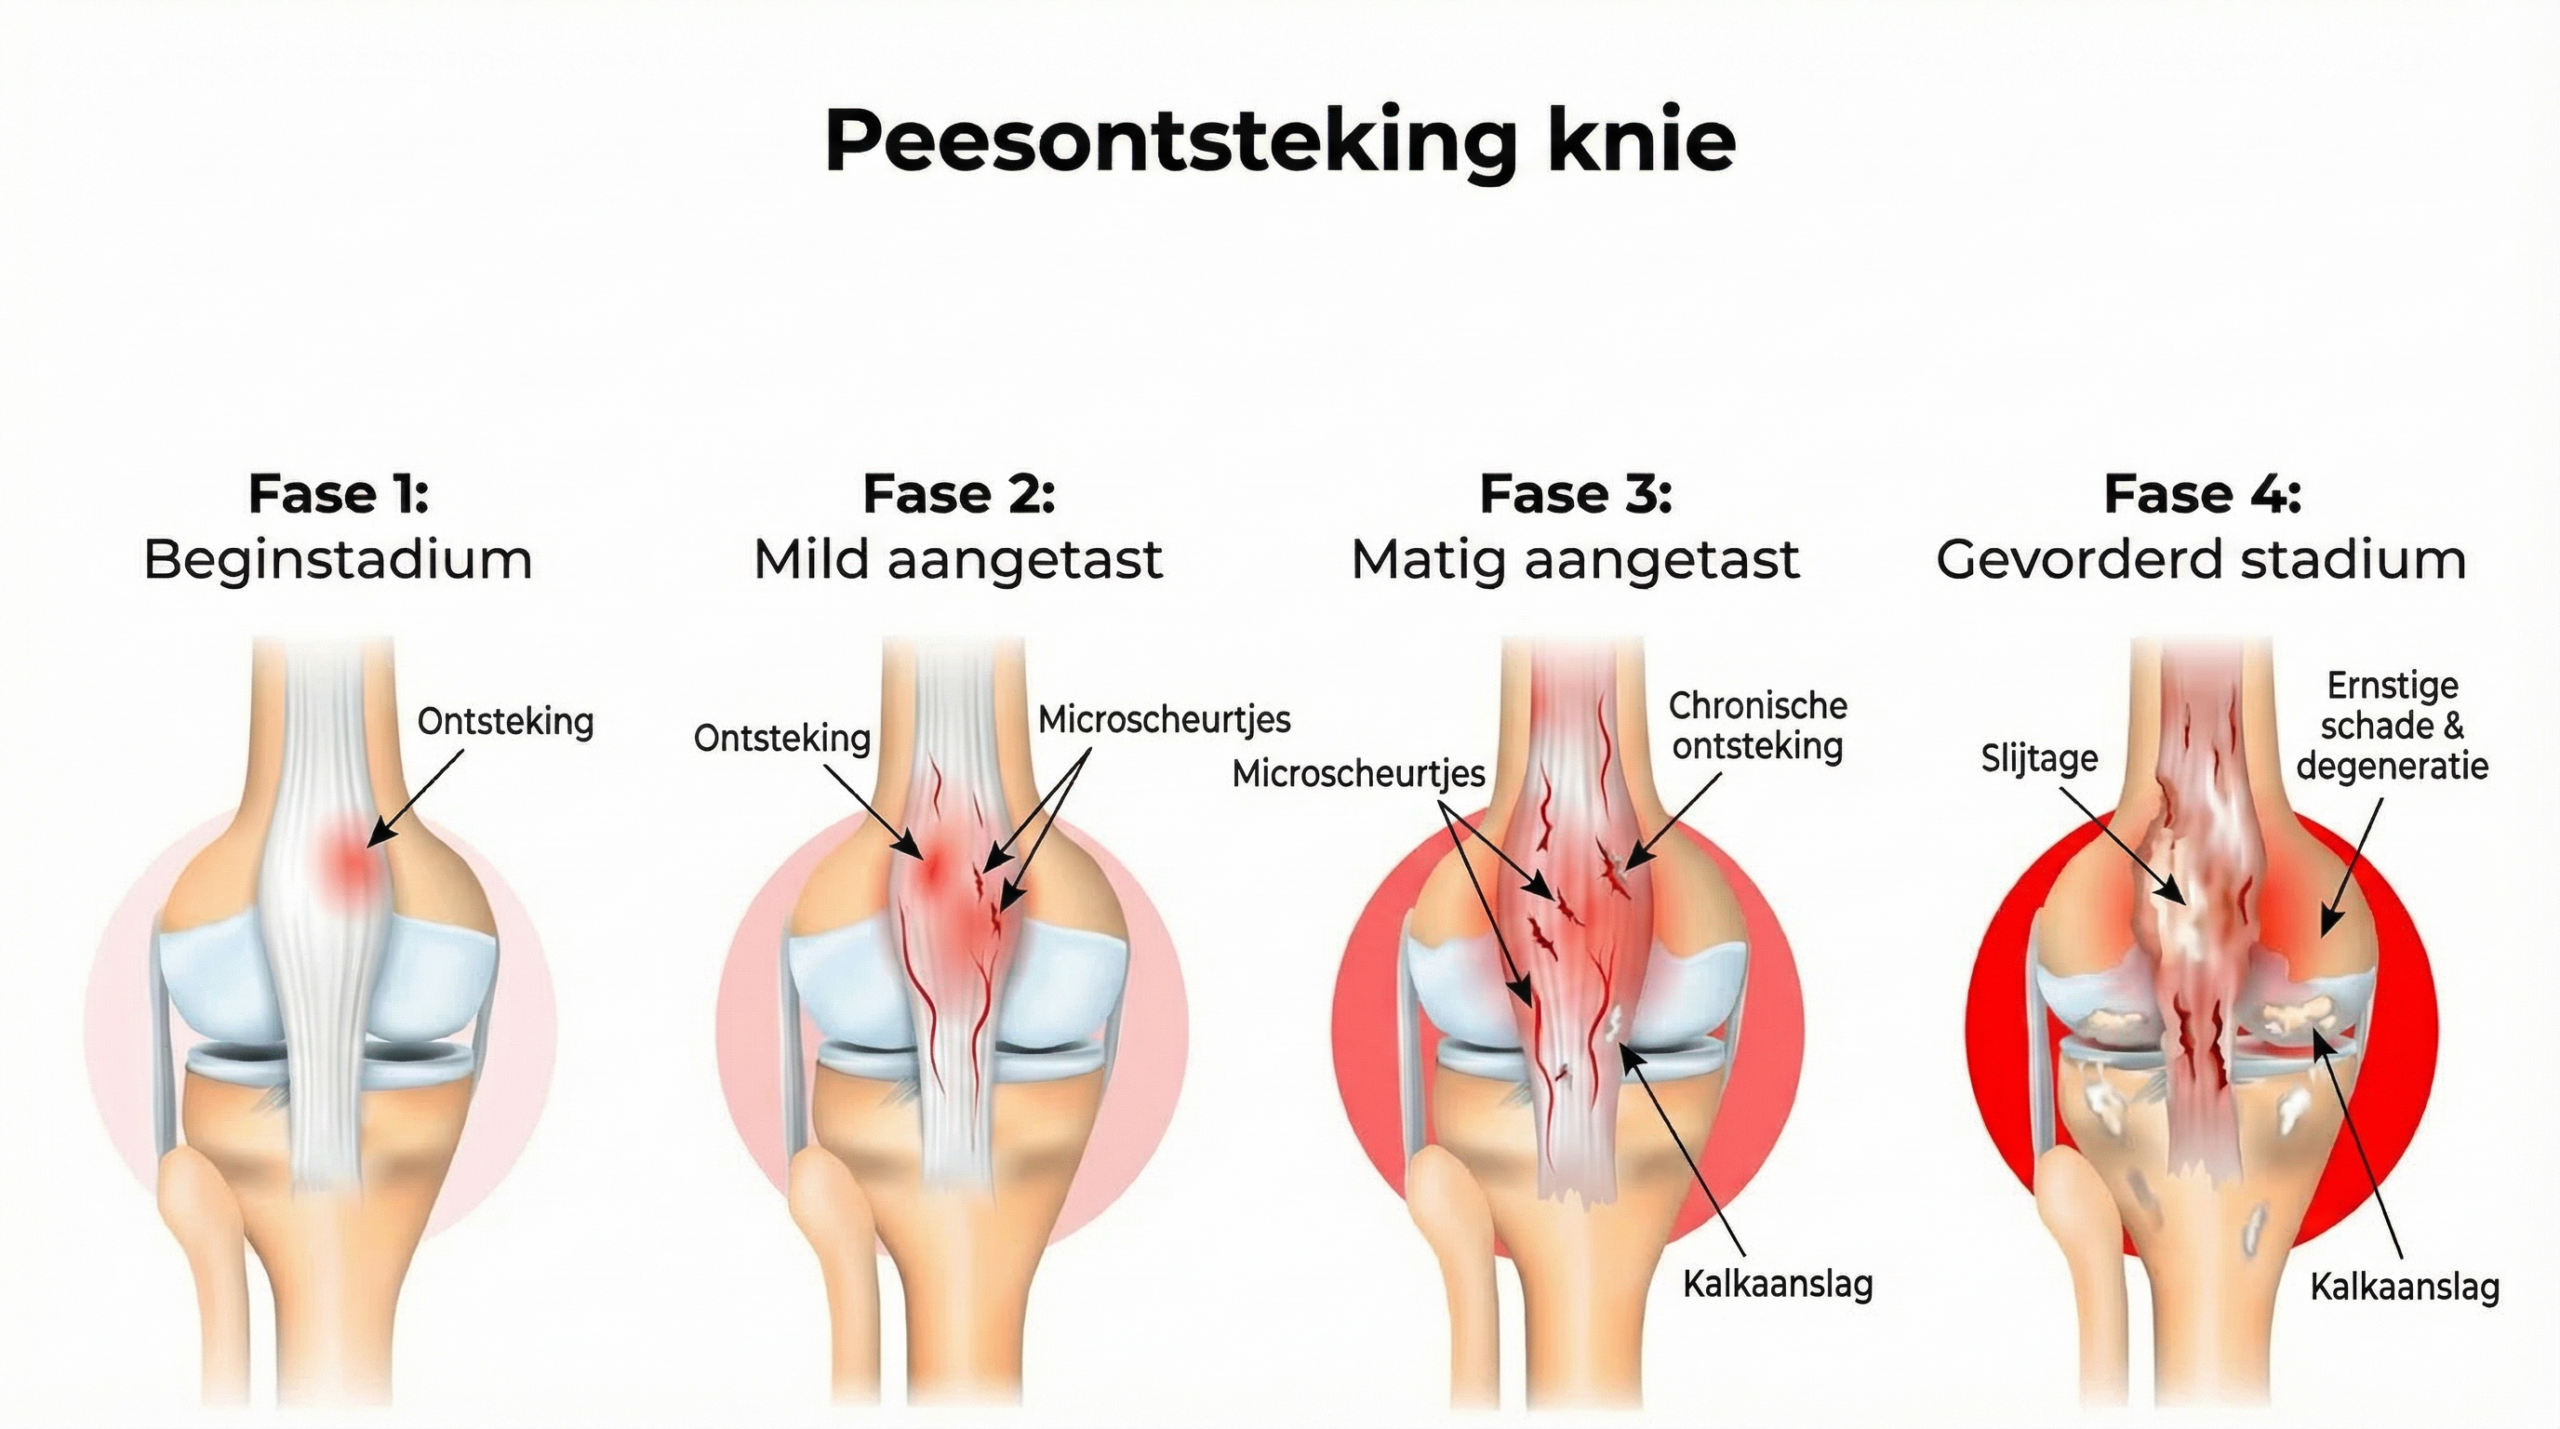

De eerste scheurtjes zijn onzichtbaar, maar bij elke dag dat de belasting aanhoudt zonder voldoende herstel, groeit de schade — en de pijn wordt progressief erger.

Maar waarom houdt die ontsteking aan?

Wanneer de kniepees herhaaldelijk wordt belast, activeren microscheurtjes pro-inflammatoire cytokinen zoals TNF-α en IL-1β.

Bij jongere mensen herstelt de pees zich nog relatief snel — maar na je veertigste neemt de kwaliteit en het aantal peescellen in de kniepees aantoonbaar af.

De ontstekingssignalen blijven actief, terwijl het herstel achterloopt.

Dit is de hoofdoorzaak van chronische peesontsteking aan de knie.

Als We De Ontsteking Aan De Knie Niet Aanpakken, Wordt Het Alleen Maar Erger

Wanneer dit gebeurt, blijft de ontsteking in de kniepees actief en neemt de structurele beschadiging toe — wat leidt tot steeds meer pijn bij elke kniebeweging.

Met de tijd wordt het eerder erger dan beter.

Stel je voor: dag na dag, terwijl de kniepees verder verzwakt, groeit de pijn — totdat dingen die je vroeger gewoon deed, zoals traplopen, opstaan uit een stoel of een wandeling maken, voelen als een enorme opgave.